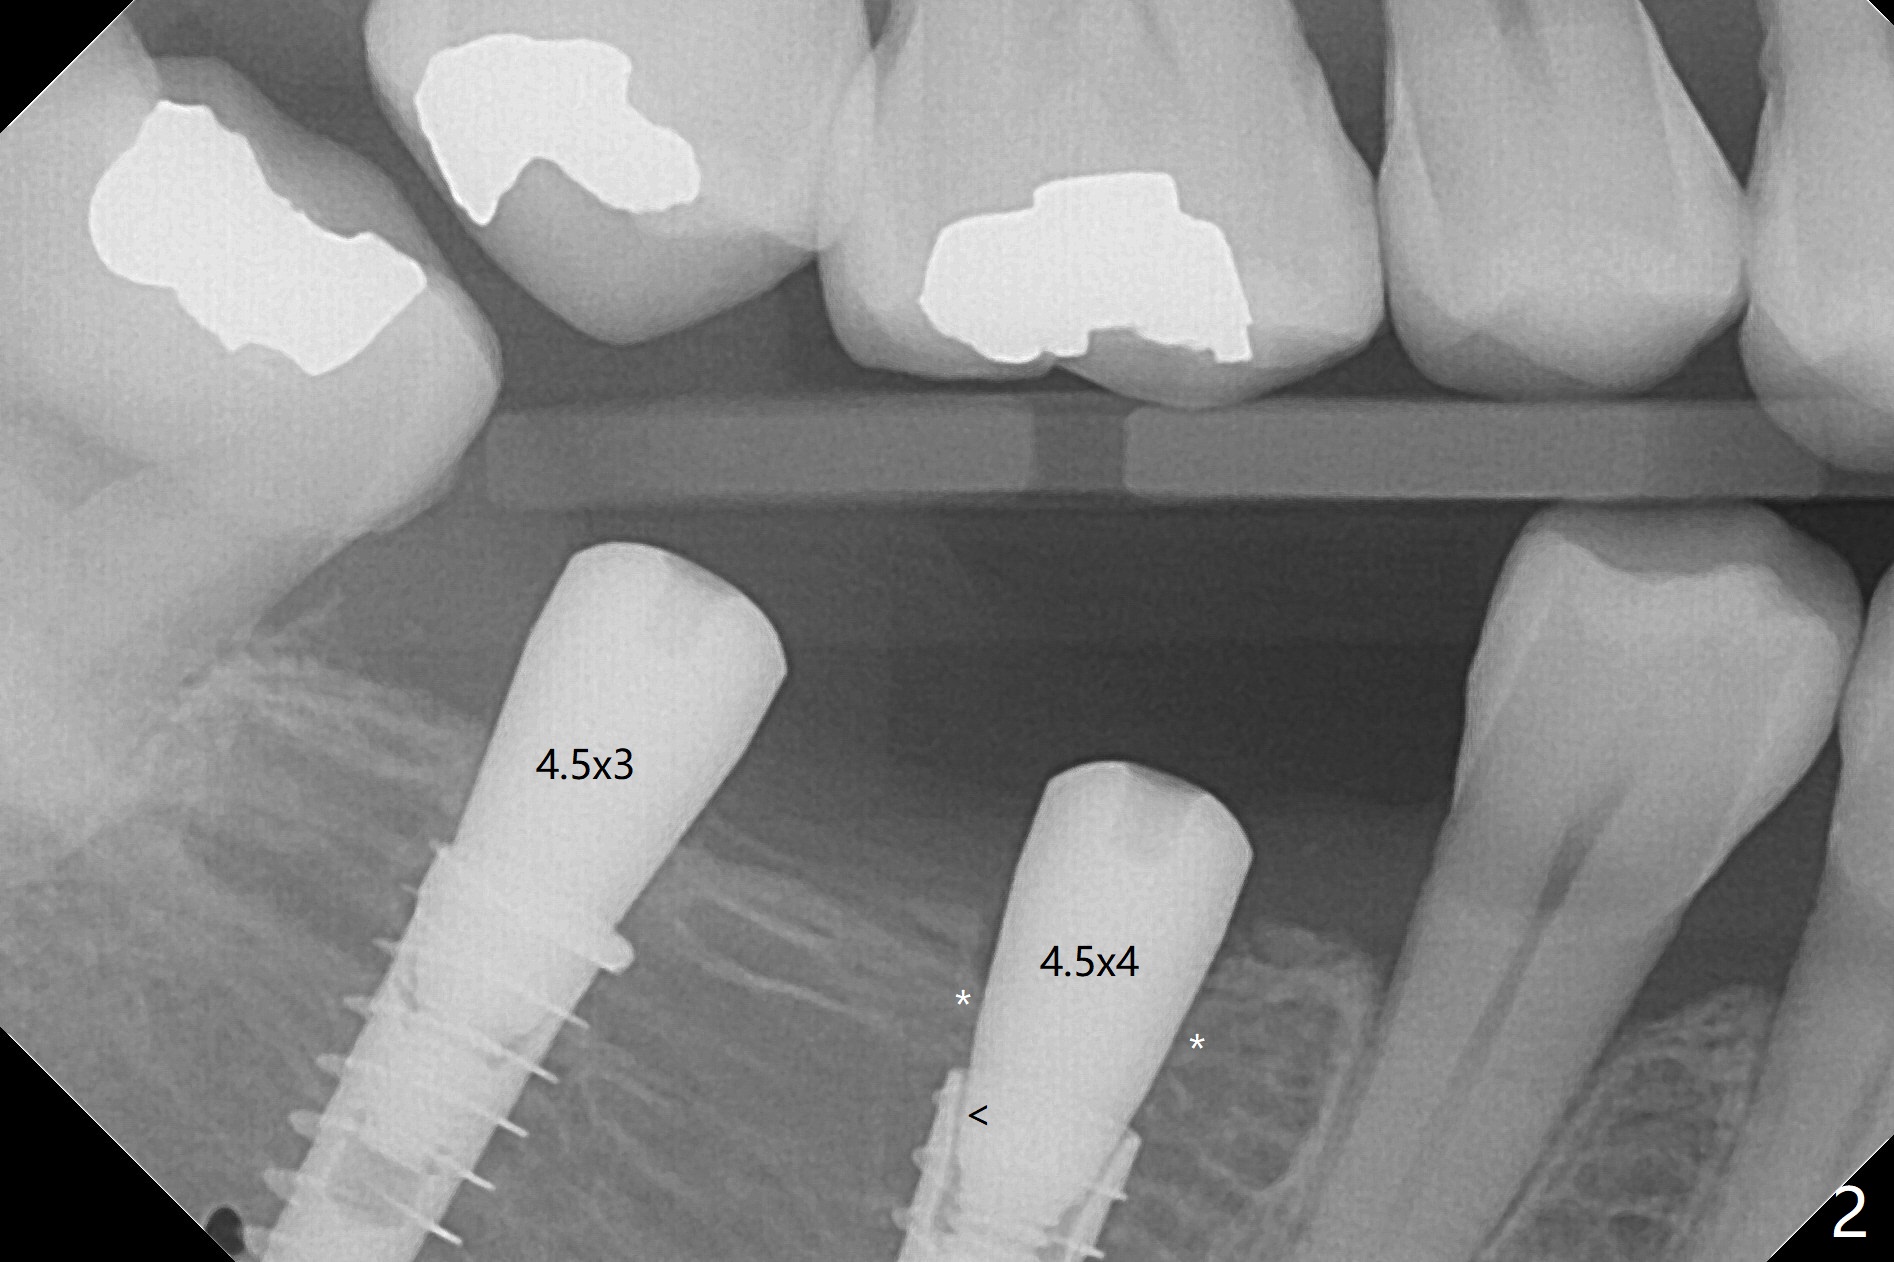

害怕病人局麻药很慢起效,术中身体会动,术中决定减小右下6,7植体直径0.5毫米(与导板设计相比),一旦植体越过牙槽嵴顶骨皮质,稳定性突然减低(图一)。尽管扭力10-15Ncm,为了避免二期手术,放置愈合基台(图二),6基台没有就位(箭头),因为植体种太深了,牙槽骨阻挡(*)基台就位。当取出6基台时,植体一起旋出,重新植入时,就没有种那么深(图三:箭头,与图一,二对比)。由于扭力低,只好放置愈合帽,骨粉(*),GEM Cap(6-9月胶原膜)和牙周胶水。由于导板设计缘故,左上5拔除,种植后,才开始左上3一段式植体植入(图四),5也植入太深(图五),必须放置最小直径最长袖(cuff)的基台(图六),今后导板即刻植牙先不要到达设计深度。术后一周CT显示尖牙植体位于牙槽骨内(图七 (>:腭侧牙槽嵴))。Bone graft fills in the buccal apical defect at #13 one week postop (Fig.8 <). 术后两个月左上3临时牙冠折裂,5松动(图九,十),后者取出衬里,软组织愈合。术后8个月左上3,5取模,右下6 uncover,愈合帽表面覆盖骨质,把7号牙愈合基台放到6号牙上,而7号牙放置4.5x4(4)毫米修复基台,固定牙周敷料,这样6号牙伤口不必缝合。术后8.5个月右下6放置4.5x7.5(4)毫米基台,发现7基台没有就位(图十一:箭头),通过旋转7 基台,终于就位(图十二),螺丝往下移位(与图十一:横线对比),但是基台边缘太低,不利于取模。改用5.5x4(5)毫米UF基台,临床上不能就位,局麻使用5.5毫米Profile Drill后,才能就位(图十三),螺丝下端超越最低螺沟(横线)。